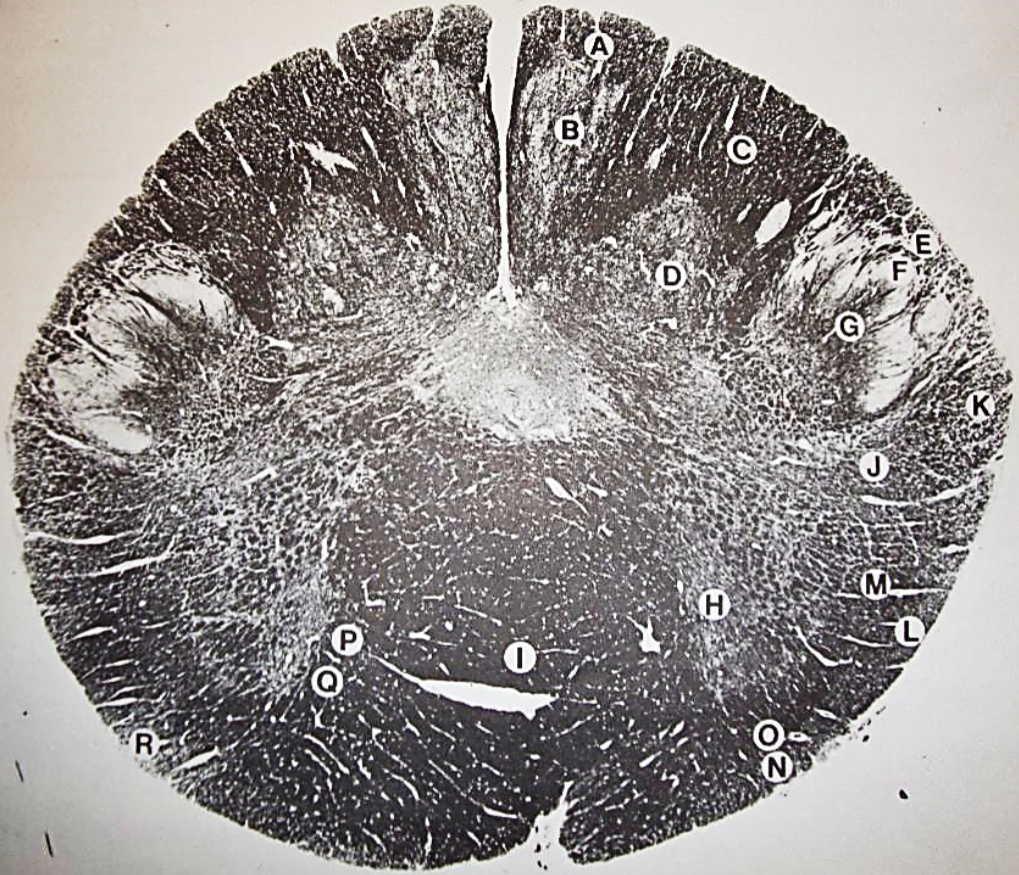

A

posterior median sulcus

B

posterior intermediate sulcus

C

anterior median fissure

D

gracile fasciculus

E

Gracile nucleus

F

fasciculus cuneatus

G

spinal trigeminal tract

H+I collectively

spinal trigeminal nucleus

J

Accessory nucleus

K

pyramidal decussation

L

lateral corticospinal tract

M

rubrospinal tract

N

posterior spinocerebellar tract

O

anterior spinocerebellar tract

P

lateral spinothalamic tract

Q

anterior spinothalamic tract

R

lateral vestibulospinal tract

S

medial longitudinal fasciculus

T

tectospinal tract

U

central canal